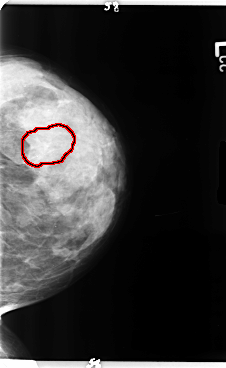

B_3358_1.LEFT_CC

LEFT_CC LINES 4784 PIXELS_PER_LINE 2936 BITS_PER_PIXEL 12 RESOLUTION 50 OVERLAY

FILE: B_3358_1.LEFT_CC.OVERLAY

TOTAL_ABNORMALITIES 1

ABNORMALITY 1

LESION_TYPE CALCIFICATION TYPE ROUND_AND_REGULAR-PUNCTATE-AMORPHOUS DISTRIBUTION REGIONAL

ASSESSMENT 3

SUBTLETY 3

PATHOLOGY BENIGN

TOTAL_OUTLINES 1

BOUNDARY